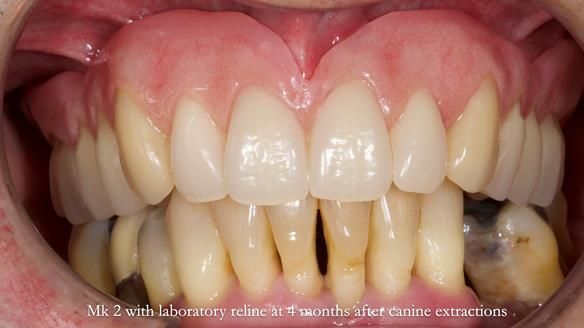

Twelve months after the final extractions, I made the Mk3 definitive complete upper denture.

Three months after fitting, a reline was carried out to adapt to tissue changes from the canine and molar extractions.